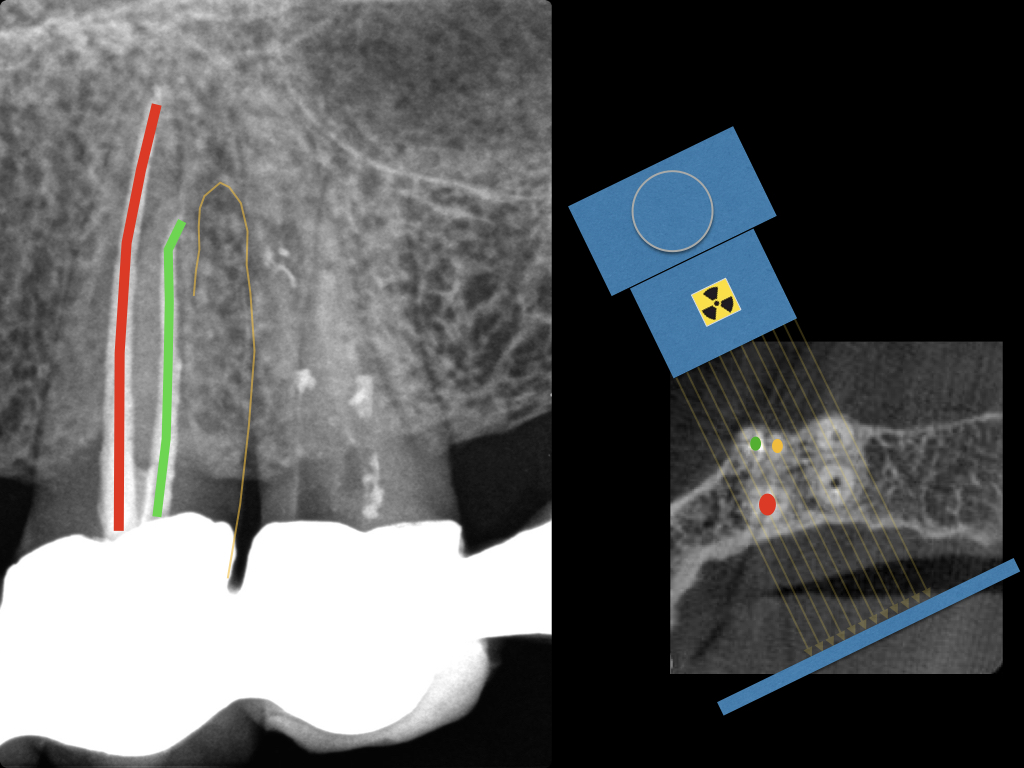

es ist zusehen.005

Es ist zu sehen … (2)